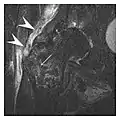

Proximal femoral fractures usually occur in osteoporotic patients, and their signs include subtle neck angulation, trabecular angulation, and subcapital impaction line. A frog-leg lateral view may be helpful if the greater trochanter is short enough. However, positioning can be difficult because of hip pain. In patients with strong suspicion of proximal femoral fracture and negative radiographs, MRI limited to coronal T1 W images and scintigraphy can be highly valuable (Figures 13 and 14). Such an option, with limited examination time, is cost-effective and allows reliable exclusion or confirmation of the diagnosis, preventing an unnecessary stay at the hospital or delayed treatment. Moreover, MRI helps to detect soft tissue abnormalities which are more frequently seen in femoral, acetabular, and pubic injuries than sacral lesions. Concomitant fractures are also frequently seen in typical pelvic sites.[1]

a

b

Figure 14: Subcapital insufficiency fracture in a 55-year-old man with a left hip pain without a history of trauma. Anteroposterior and Lauenstein view radiographs centered on the left hip do not show an obvious fracture line, but mild acetabular osteophytosis was noted consistent with hip osteoarthritis (not shown). (a) Coronal T1-weighted MRI shows a linear low-signal band through the femoral neck corresponding to a fracture line (arrowheads). (b) Bone scintigraphy shows focal uptake (arrow) corresponding to the fracture.[1]